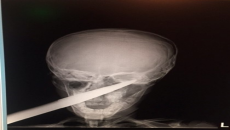

Катерушка падна върху главата на 4-годишно момиченце в детска градина

Метална катерушка в двора на детска градина падна върху главата на 4-годишно дете. Инцидентът е станал в Асеновград, съобщава Дарик.  Децата си играели, когато изведнъж катерушката се наклонила и паднала върху главата на момиченцето.Веднага след инц...